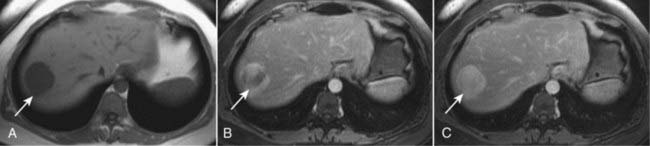

Figure 18-34 Cavernous hemangioma of the liver, MRI.

(A) This image (an axial T1-weighted image) demonstrates a well-circumscribed, slightly lobular dark mass in the right hepatic lobe (solid white arrow in all images). (B) Subsequent images following the administration of intravenous contrast (gadolinium) show peripheral-to-central enhancement, until the entire mass homogeneously enhances on a delayed 10-minute image (C). The combination of this enhancement pattern and the signal characteristics of the lesion allows an unequivocal diagnosis of hemangioma.